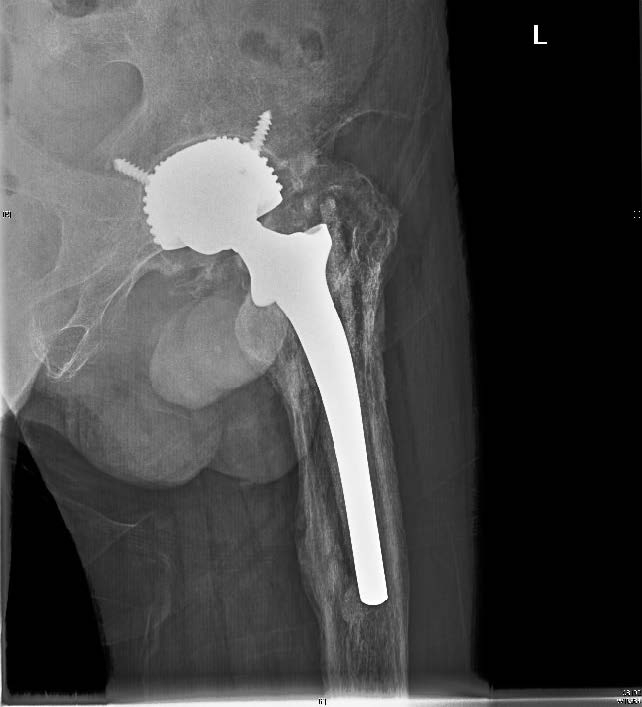

图1 患者男,66 岁,术前髋关节X 线正位片示:左侧人工全髋关节置换术后髋臼假体松动,股骨假体下沉,髋周骨质疏松

图2 同一患者,翻修术后第2 天双髋X 线片示远端固定长柄生物MP 假体位置良好